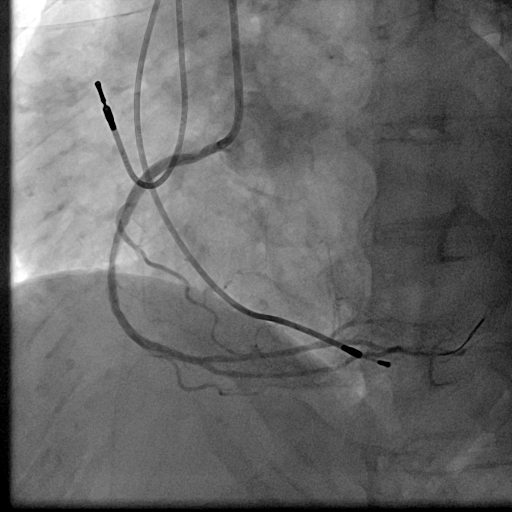

We used 7Fr JR3.5SH guiding and SION blue ES wire. Wire was easily crossed, and IVUS showed in-stent restenosis with neointimal hyperplasia and underexpanded stent. Long inflation technique using cutting balloon was performed, and Biolimus-A9 coated stent was deployed for in-stent lesion. Post dilation using NC balloon was performed, and procedure was completed. 4 months and 1year and 9 months after the procedure, follow up CAG with coronary angioscopy was performed.

1 year and 2 months after the initial procedure using underexpanded stent for eccentric calcified plaque placed at RCA ostium, in-stent restenosis was occurred. PCI was performed with drug-coated balloon and another 8 months later, re-restenosis was occurred. PCI was performed again with Biolimus-A9 coated stent deployed for in-stent lesion. 4 months, and 1 year and 9 months after the stent implantation, CAG was performed with evaluating coronary angioscopy. At the 4 months later, there was no restenosis and we confirmed beginning of neointima coverage for stent strut. At the 1 year and 9 months later, there was also no restenosis, and we confirmed enough and optimal neointimal coverage as vessel healing after stent implantation. Biolimus-A9 coated stent has early drug release system and polymer-free characteristics. The characteristics of the stent may have contributed to get the early smooth and optimal neointimal coverage, and the prevention of malignant cycle of RCA ostium in-stent restenosis.